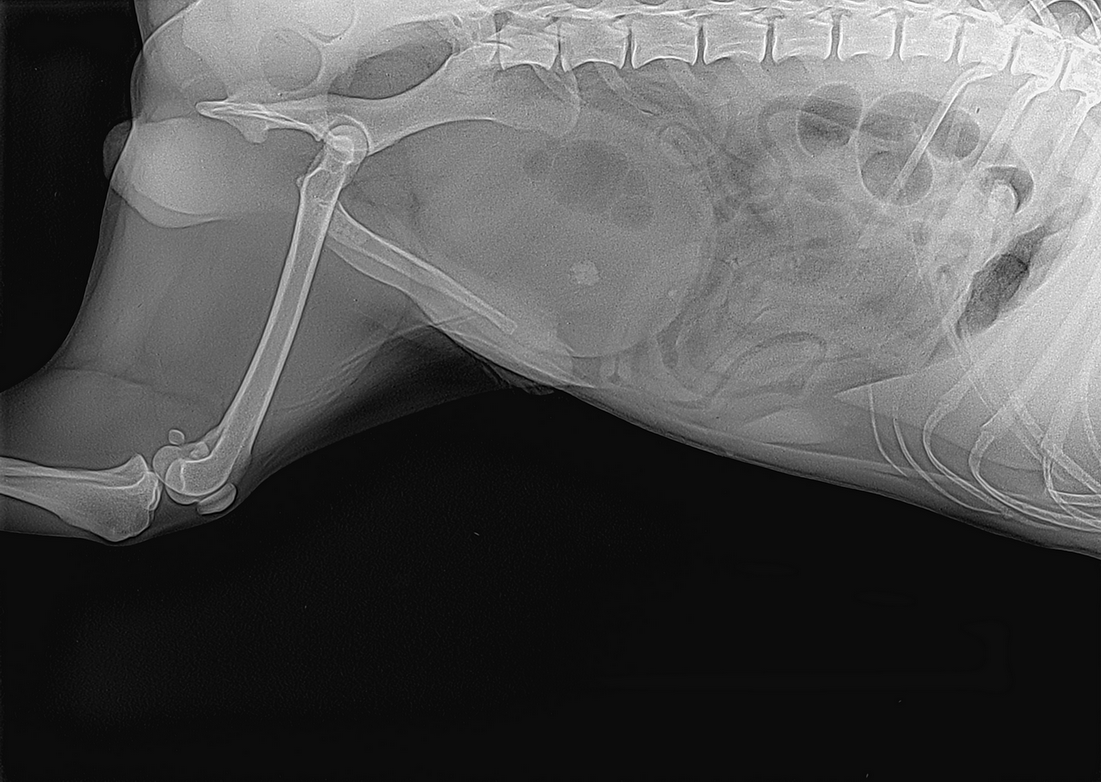

Pojav krvi v urinu pri samčkih je lahko posledica vnetja žleze prostate, ki lahko psom v zrelih in poznih letih dela velike težave. Žleza nabrekne, v njej se pogosto pojavijo ciste, ki občasno izločajo kri v sečnico. Značilno za težave s prostato je, da se pojavi kri iz spolovila tudi brez uriniranja. Lastniki psa kar nenadoma opazijo krvave kapljice po tleh, pri podrobnem pregledu pa ugotovijo, da mu kri občasno kaplja iz penisa. Pojav krvi v urinu ali krvavitev iz penisa je pri kužkih vedno resen pojav, ki zahteva takojšen pregled pri veterinarju oziroma veterinarski ustanovi, ki je opremljena za internistično diagnostiko. Pri ugotavljanju vzroka krvavitve si pomagamo z laboratorijem za diagnostiko krvi in urina, rentgenskim slikanjem in ultrazvočno preiskavo. S krvno sliko ugotavljamo prisotnost vnetja, ugotavljamo prizadetost ledvic, kar je izrednega pomena za določitev terapije. Z rentgenskim slikanjem in ultrazvočno preiskavo pa ugotavljamo morfološke spremembe na mehurju, ledvicah, prostati in prisotnost kamnov.